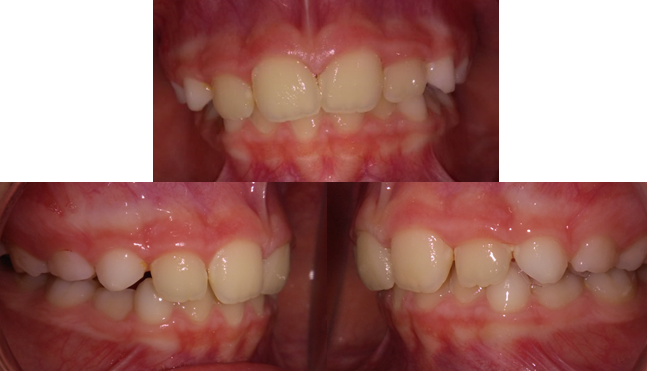

Se planificó una disyunción y brakets durante un año. La disyunción es un aparato que consigue realizar la expansión del maxilar superior o del paladar de una manera muy rápida(6 meses) y con una tasa de recaídas muy baja. Los brakets se programaron para alinear los dientes después de la expansión para mejorar su posición y estética(preocupación fundamental de la madre) y lo realmente importante, evitar que pudiesen provocar desvíos funcionales de la mandíbula que arruinasen el efecto de la disyunción.

Los efectos de la disyunción fueron mucho mejor de los esperados. Tras la expansión los incisivos se colocaron espontáneamente en una posición casi perfecta. De hecho los brakets no se llegaron a colocar porque no merecía la pena colocar los dientes mejor de lo que estaban ya que no estaban generando ningún desvío funcional de la mandíbula y lo más importante, ¡¡la madre estaba encantada con el resultado en ese momento!! Así pues un tratamiento de ortodoncia que se había planificado para un año se redujo a la mitad. Lo mejor de todo es que la niña seguía sonriendo igual de contenta que el primer día.

Foto 2: Final del tratamiento.